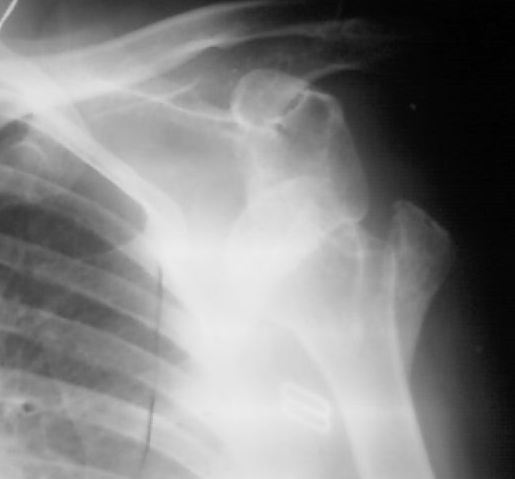

Обратилась девушка 30 лет с жалобами на боли и ограничение движений в левом плечевом суставе.

На рентгенснимке левого плеча в передне-задней проекции полный вывих плеча с отрывом

большого бугорка. Пальпаторно головка под клювовидным отростком лопатки. Со слов девушки,

6 месяцев назад получила травму, упала на область левого плеча с высоты примерно 2 метров. За